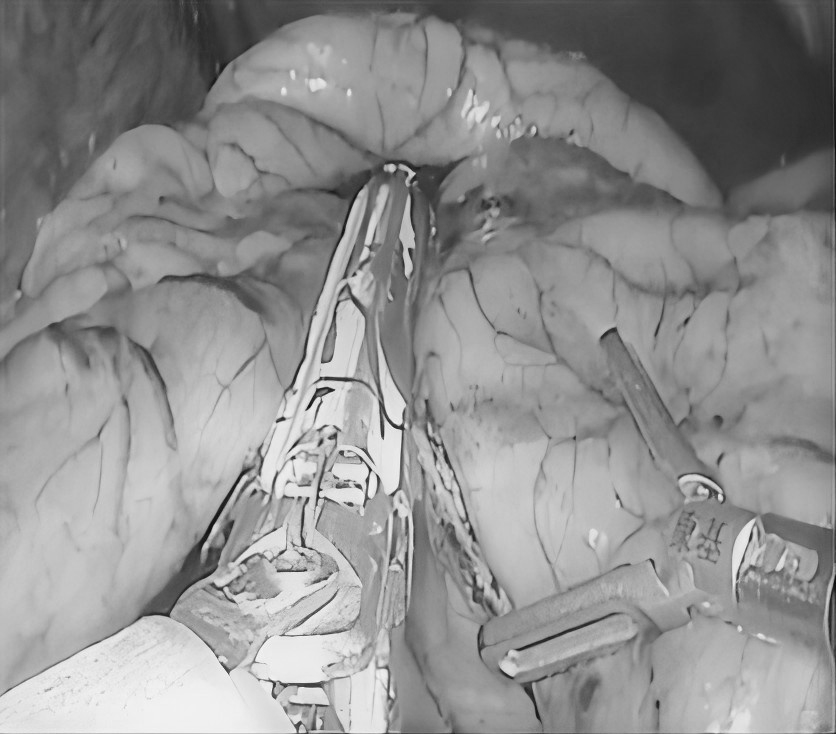

是不是一上厕所就 “见红” 久坐不动后屁股 又痛又痒 别害羞 这可能是痔疮在作怪! 今天贵州航天医院普外科就和大家唠唠这个“难言之隐”,教大家怎么科学应对,轻松告别烦恼! 痔疮是啥? 痔疮不是大病,但遭罪!简单来说,就是肛门附近的血管肿胀了(肛门和直肠部位的静脉曲张),或者是因长期便秘、久坐等原因肛垫被"压垮"了,逐渐下移脱出肛门,里面的血管组织就会像被挤压的海绵一样肿胀起来,形成痔疮。一般分三种: 内 痔:藏在里面,悄悄出血不疼,但擦纸见红要警惕! 外 痔:长在门口,摸得到小肉球,疼起来坐立不安! 混合痔:里外夹击,又出血又疼,简直“雪上加霜”! 这些信号正在提示你: 痔疮可能找上门! 便 血:排便时出现鲜红色血液。 肛门疼痛:排便像“拉玻璃渣”,久坐后更难受! 肛门瘙痒:总想挠,越挠越痒,因分泌物刺激皮肤引起。 脱 出:严重时痔核掉出来。 为啥会得痔疮? 这些习惯你中招没? (一)久坐久站:打工人、司机、老师等群体注意!一坐、一站就是一天,血管压力大! (二)饮食不当:火锅烧烤天天造?菊花火辣辣警告! (三)便秘或腹泻:蹲坑刷手机半小时?肠道抗议了! (四)妊 娠:宝宝压肚子,孕期腹压增高。 (五)遗传因素:家族有痔疮病史?得多留个心眼! 预防痔疮,记住这5招! (一)吃对东西:蔬菜水果粗粮管够,拉粑粑顺畅不费劲! (二)每天多喝水(1500-2000毫升):大便不干硬,菊花少受罪! (三)别当“木头人”:每坐1小时,起来活动5分钟。 (四)养成良好蹲坑习惯:蹲坑时间不得过长,3-5分钟最合适! (五)提肛运动:偷偷练!每天收缩肛门5秒再放松(50次左右),增强肛门肌肉力量。 痔疮能治吗? 方法比你想的简单! (一)轻症自救 1.使用痔疮膏、塞栓剂等药物,消肿止痛。 2.温水坐浴+多休息,促进血液循环,有助缓解。 (二)重症别硬扛 1.微创手术(如吻合器痔上黏膜环切术、激光治疗),创伤小,恢复快。 2.传统手术直接切除痔核。 关于痔疮的3大谣言, 别再信了! (一)“痔疮会自己好?”→拖久了可能更严重! (二)“便血就是痔疮?”→肠癌也会便血,要及时去医院! (三)“手术疼死人?”→现在微创技术创伤小、恢复快,无需过度担心。 出现这些情况,立马去医院! 1.便血止不住。 2.肛门疼到睡不着,走路都困难。 3.掉出来塞不回去,卡住发紫。 痔疮虽常见,但科学防治是关键!管住嘴、迈开腿、别久坐,发现问题早治疗!记住,健康菊花才能让你“畅通无阻”,笑对生活! 注:图片来源于网络,如有侵权,请联系删除。 贵州航天医院普外科专家团队 梁 跃 普外科主任 主任医师 临床擅长:对普外科各类肿瘤手术具有丰富的临床经验。 毕业于遵义医学院,遵义市医学会小儿外科学分会常务委员,遵义市肛肠协会理事,遵义市医学会核医学分会(第二届)委员会委员;荣获第三期“黔医人才计划”优秀学员称号;主持市级课题1项,完成省级课题1项,在国内各类刊物上发表论文10余篇。 钱科洪 普外科 副主任医师 临床擅长:从事普外科临床工作30余年,对各类普外科疾病的诊治、乳腺、甲状腺、胃十二指肠、结直肠等疾病及疑难杂症具有丰富的临床诊疗经验。 毕业于遵义医学院临床医疗系,2009年前往中山大学附属第一医院微创外科进修学习,在国内各专业期刊发表论文数篇。 贵州航天医院普外科简介 基本情况 贵州航天医院普外科成立于1968年,前身属于航天部O61基地3417医院外一科,1998年3417医院、3427医院合并后更名为普外科,下设胃肠外科、肛肠外科2个亚专业科室,拥有专科设备和技术,是中国疝病专科联盟单位,贵州医科大学附属医院胃肠外科专科联盟单位。开放床位40张,配备医护人员21人。 专科特色 普外科致力于胃肠及肛肠疾病的外科临床诊治及科研,以腹腔镜微创外科技术为本,形成以快速康复治疗胃肿瘤、结直肠肿瘤、小肠肿瘤、直肠脱垂、肥胖病、急腹症、各类疝、痔、瘘等专科特色,同时注重胃肠疾病尤其是结直肠恶性肿瘤的基础研究和临床转化研究。 开展手术:腹腔镜下胃癌根治术,腹腔镜下袖状胃切除术,腹腔镜下胃肠道间质瘤切除术,腹腔镜下结、直肠癌根治术,胃癌、结直肠癌的精准治疗,腹腔镜下小儿疝气、成人疝修补术,腹腔镜下阑尾手术,内痔的硬化注射治疗及痔疮的微创治疗:ATH、PPH、TST,直肠脱垂的各种手术治疗,难治性伤口VSD技术,鼻胃肠管、肠梗阻导管置入术,肛肠术后间歇性导尿技术,并引进了中医适宜技术,也为各种化疗患者提供输液港安装,提高患者就医体验。 腹腔镜下腹股沟疝无张力修补术 腹腔镜下腹股沟疝 无张力修补术 腹股沟疝里金斯坦(Lichtenstein)手术 PPH微创术治疗环状混合痔 黏连性或炎性肠梗阻-肠梗阻导管 腹腔镜袖状胃切除 腹腔镜阑尾切除术 腹腔镜阑尾肿瘤切除术 腹腔镜下结肠癌根治术 诊疗范围 胃肿瘤、结直肠肿瘤、小肠肿瘤、肥胖症、各类急腹症、腹部外伤、腹壁疝、便秘、直肠脱垂、痔疮、肛瘘、肛裂等胃肠、肛肠外科疾病。 END